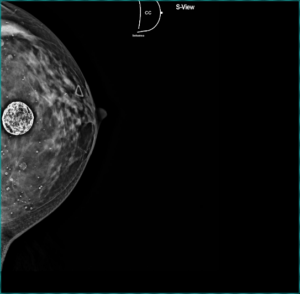

Tomosíntesis con proyección cráneo-caudal de mama izquierda